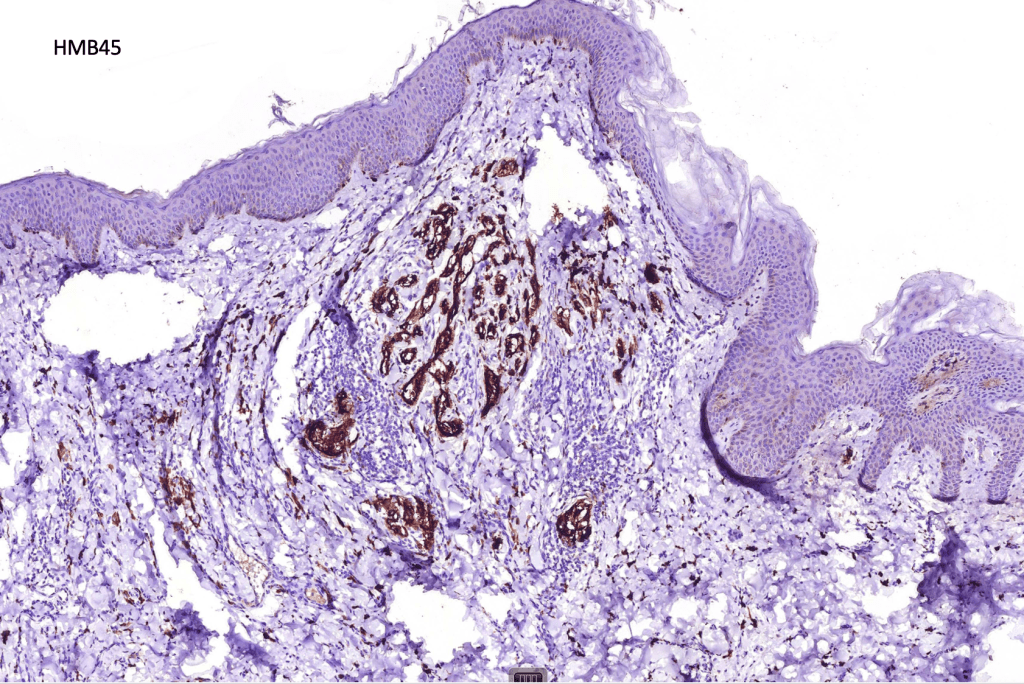

•S100 & HMB45 +ve